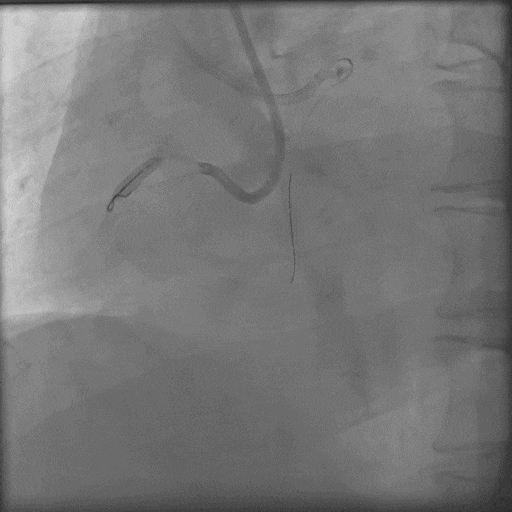

4.病例:如何开通近段纤维帽难以突破、微导管、预扩球囊难以通过的右冠CTO?

62岁,男性患者,间断胸痛1月,冠脉CTA提示右冠闭塞伴1-2段严重钙化;造影示右冠CTO,无明显入路且迂曲钙化,着陆区可

预案正向找到血管结构,ADR术式可快速高效开通右冠CTO,即使走逆向,也得进行充分正向准备,以进行Reverse-Cart;选择7F-AL1强支撑指引导管,由于近端纤维帽坚硬, Gaia3导丝、P200导丝前向试探失败;XTA、P200导丝Knuckle失败;